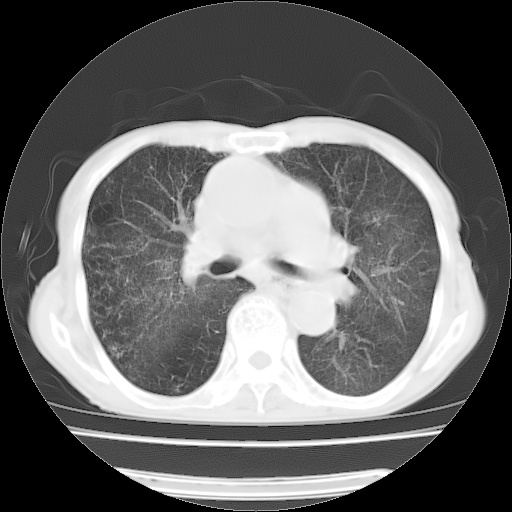

病人发热、气促就诊。原二周前已行ct扫描,当时诊断为双肺下叶、右肺中叶支气管扩张并感染,双肺上叶片状渗出性病变。今天复查胸部ct,双肺下叶支气管扩张并感染病灶较前明显吸收,但双肺上叶渗出性病变较范围较前明显增大。

现传今天ct图像给大家讨论。

双肺多发大片状、斑片状高密度渗出影,部分实变,考虑病毒性肺炎。